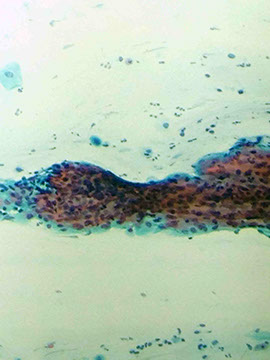

Lymphoid follicle

Follucular cervicitis

Group containing mostly lymphocytes of the small and sometimes large variety; can see tangible body macrophages in there sometime too

- tangible body macrophages are a clue for chronic folicular cervicitis

Follicular cervicitis

tangle of small blue cells c high NC ratios

- admixed histiocytes and dendritic cells c pale nuclei

- may be assoc c Chlyamydia trachomatis